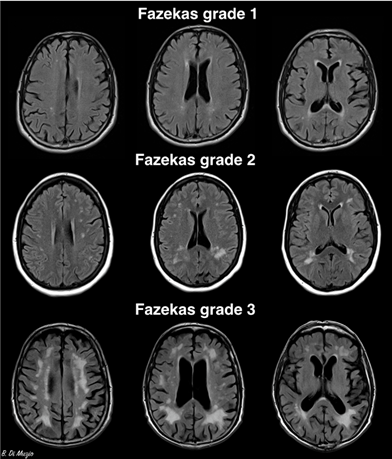

评估方法主要有两种:改良Fazekas法(3级)、人工智能计算脑白质高信号体积